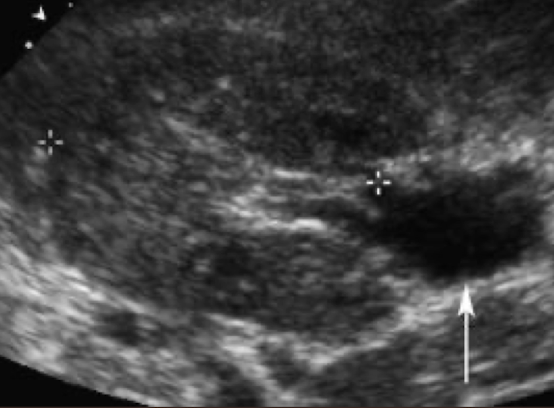

SONO: medullary cystic kidney disease (MCKD)

hyperechoic calyces with or without stones

??

medullary cystic kidney disease

calcium deposits in calyces

medullary nephrocalcinosis (medullary cystic kidney disease)

calcium deposits in medulla (heart-shaped ♥)

cortical nephrocalcinosis (medullary cystic kidney disease)

calcium deposits in cortex